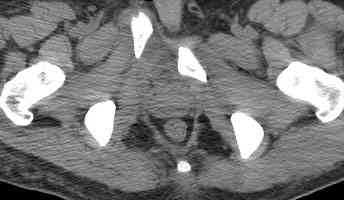

Уважаемые коллеги! опять вопрос по повреждению таза. Больной получил производственную травму 10 дней назад - удар балкой около 3 тонн в область верхней трети правого бедра и лона.

Был диагностирован перелом "типа бабочки" и повреждение уретры. Сделана цистостома. У насв отделении 3 дня. Имеется огромная флюктуирующая гематома с "галифе"-образной деформацией обеих бедер. Пнкционно эвакуировали в несколько приемов из подфасциальных полостей на бедрах около 3 литров геморрагического отделяемого с последующей эластической компрессией. При пункциях выявлено сообщение полостей на бедрах - видимо через поравннуюдиафрагму дна и полость таза - при удалении крови справа уменьшался объем левого бедра. Какой то активности проявялять покабоимся - аппаратная фиксация через отслоенные ткани представляется чреватой нагноением, открытая фиксация в условиях такой гематомы тоже не радует. Хотелось бы услышать ваше мнение

Типичная картина Morel-Lavallee повреждения.

Безуспешны многочисленные шприцевые эвакуации, мы лечим в операционной, доступом на латеральной поверхности, открытием образования с удалением и очисткой полости щеткой. Закрываем с дренажной трубкой (в архивах сайта) и накладывается мягкая повязка Спика из нескольких слоев эластичной повязки.